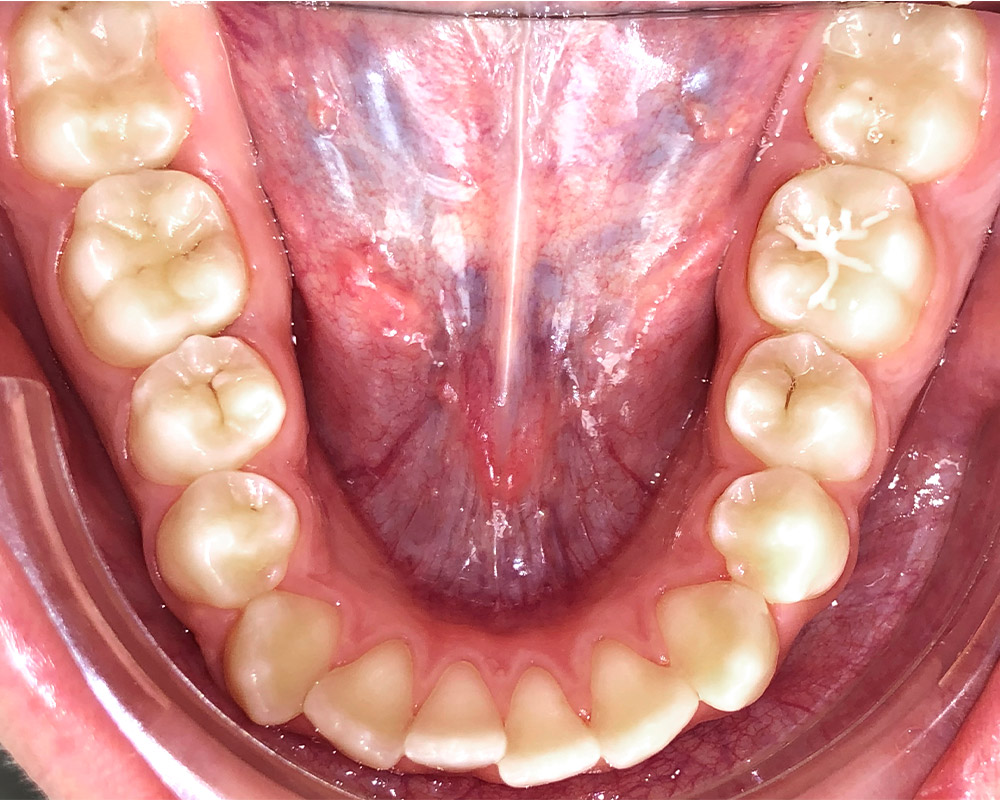

Кейс 16

Акинфиева

Количество кап ВЧ 20

Количество кап НЧ 20

ДО

ПОСЛЕ